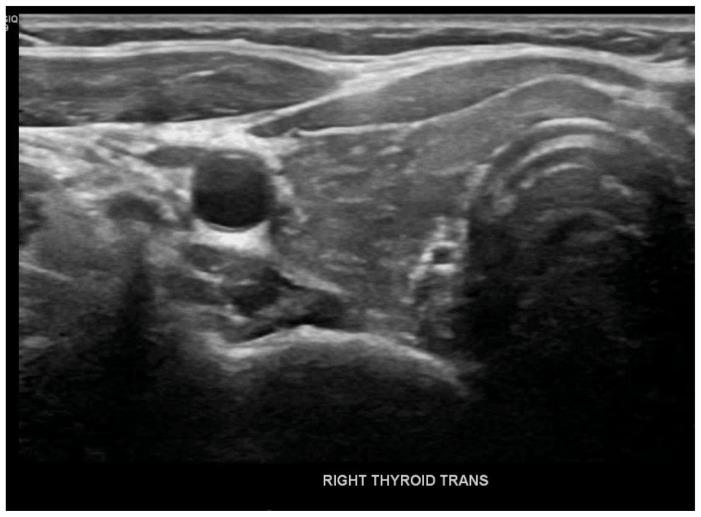

Immune Checkpoint inhibitors (ICIs) such as nivolumab, pembrolizumab, and ipilimumab are monoclonal antibodies against cytotoxic T lymphocyte antigen 4 (CTLA4) or program death (PD)1 and its ligand PDL1. Agents targeting PD1, such as pembrolizumab, have shown widespread efficacy in the past and are also associated with a wide range of immune-related adverse events (irAEs), including endocrine toxicities. A 31-year-old female with a medical history significant for Stage IIb Breast cancer on chemo and immunotherapy (pembrolizumab) presented with nausea, vomiting, and generalized abdominal pain. Laboratory studies showed a blood glucose level of 356 mg/dl, elevated Anion gap 18 meq/L, beta-hydroxybutyrate 46 mg/d, and low C-peptide levels <0.10 ng/ml. The patient was treated for Diabetic Ketoacidosis (DKA). Further testing revealed high Thyroid Stimulating Hormone (TSH) levels along with elevated thyroid peroxidase levels of 38 IU/L. After discharge from the hospital on insulin and levothyroxine therapy, the patient reported increasing fatigue and further testing revealed low cortisol levels <0.5 mcg/dl with elevated ACTH consistent with primary adrenal insufficiency. The patient was started on hydrocortisone therapy with improvement in symptoms. Endocrine toxicities are not uncommon in patients receiving pembrolizumab, but polyendocrinopathy in a relatively rare side effect of pembrolizumab. Only a few cases of pembrolizumab-induced polyendocrinopathy have been reported so far which we have mentioned in this article. While patients are on immunotherapy, close monitoring for clinical signs & symptoms can lead to an early diagnosis, substantially improving morbidity and mortality.

免疫检查点抑制剂(ICIs),如纳武单抗、帕博利珠单抗和伊匹木单抗,是针对细胞毒性T淋巴细胞抗原4(CTLA4)或程序性死亡(PD)1及其配体PDL1的单克隆抗体。靶向PD1的药物,如帕博利珠单抗,过去已显示出广泛的疗效,并且还与多种免疫相关不良事件(irAEs)相关,包括内分泌毒性。一名31岁女性,有IIb期乳腺癌病史,正在接受化疗和免疫治疗(帕博利珠单抗),出现恶心、呕吐和全腹痛。实验室检查显示血糖水平为356mg/dl,阴离子间隙升高至18meq/L,β-羟丁酸为46mg/d,C肽水平低<0.10ng/ml。该患者接受了糖尿病酮症酸中毒(DKA)治疗。进一步检查发现促甲状腺激素(TSH)水平升高,同时甲状腺过氧化物酶水平升高至38IU/L。出院后接受胰岛素和左甲状腺素治疗,患者报告疲劳加剧,进一步检查发现皮质醇水平低<0.5mcg/dl,促肾上腺皮质激素(ACTH)升高,符合原发性肾上腺功能不全。患者开始接受氢化可的松治疗,症状有所改善。内分泌毒性在接受帕博利珠单抗治疗的患者中并不罕见,但多内分泌病是帕博利珠单抗相对罕见的副作用。迄今为止,仅报道了少数几例帕博利珠单抗诱导的多内分泌病病例,我们在本文中已提及。当患者接受免疫治疗时,密切监测临床体征和症状可实现早期诊断,大幅提高发病率和死亡率。